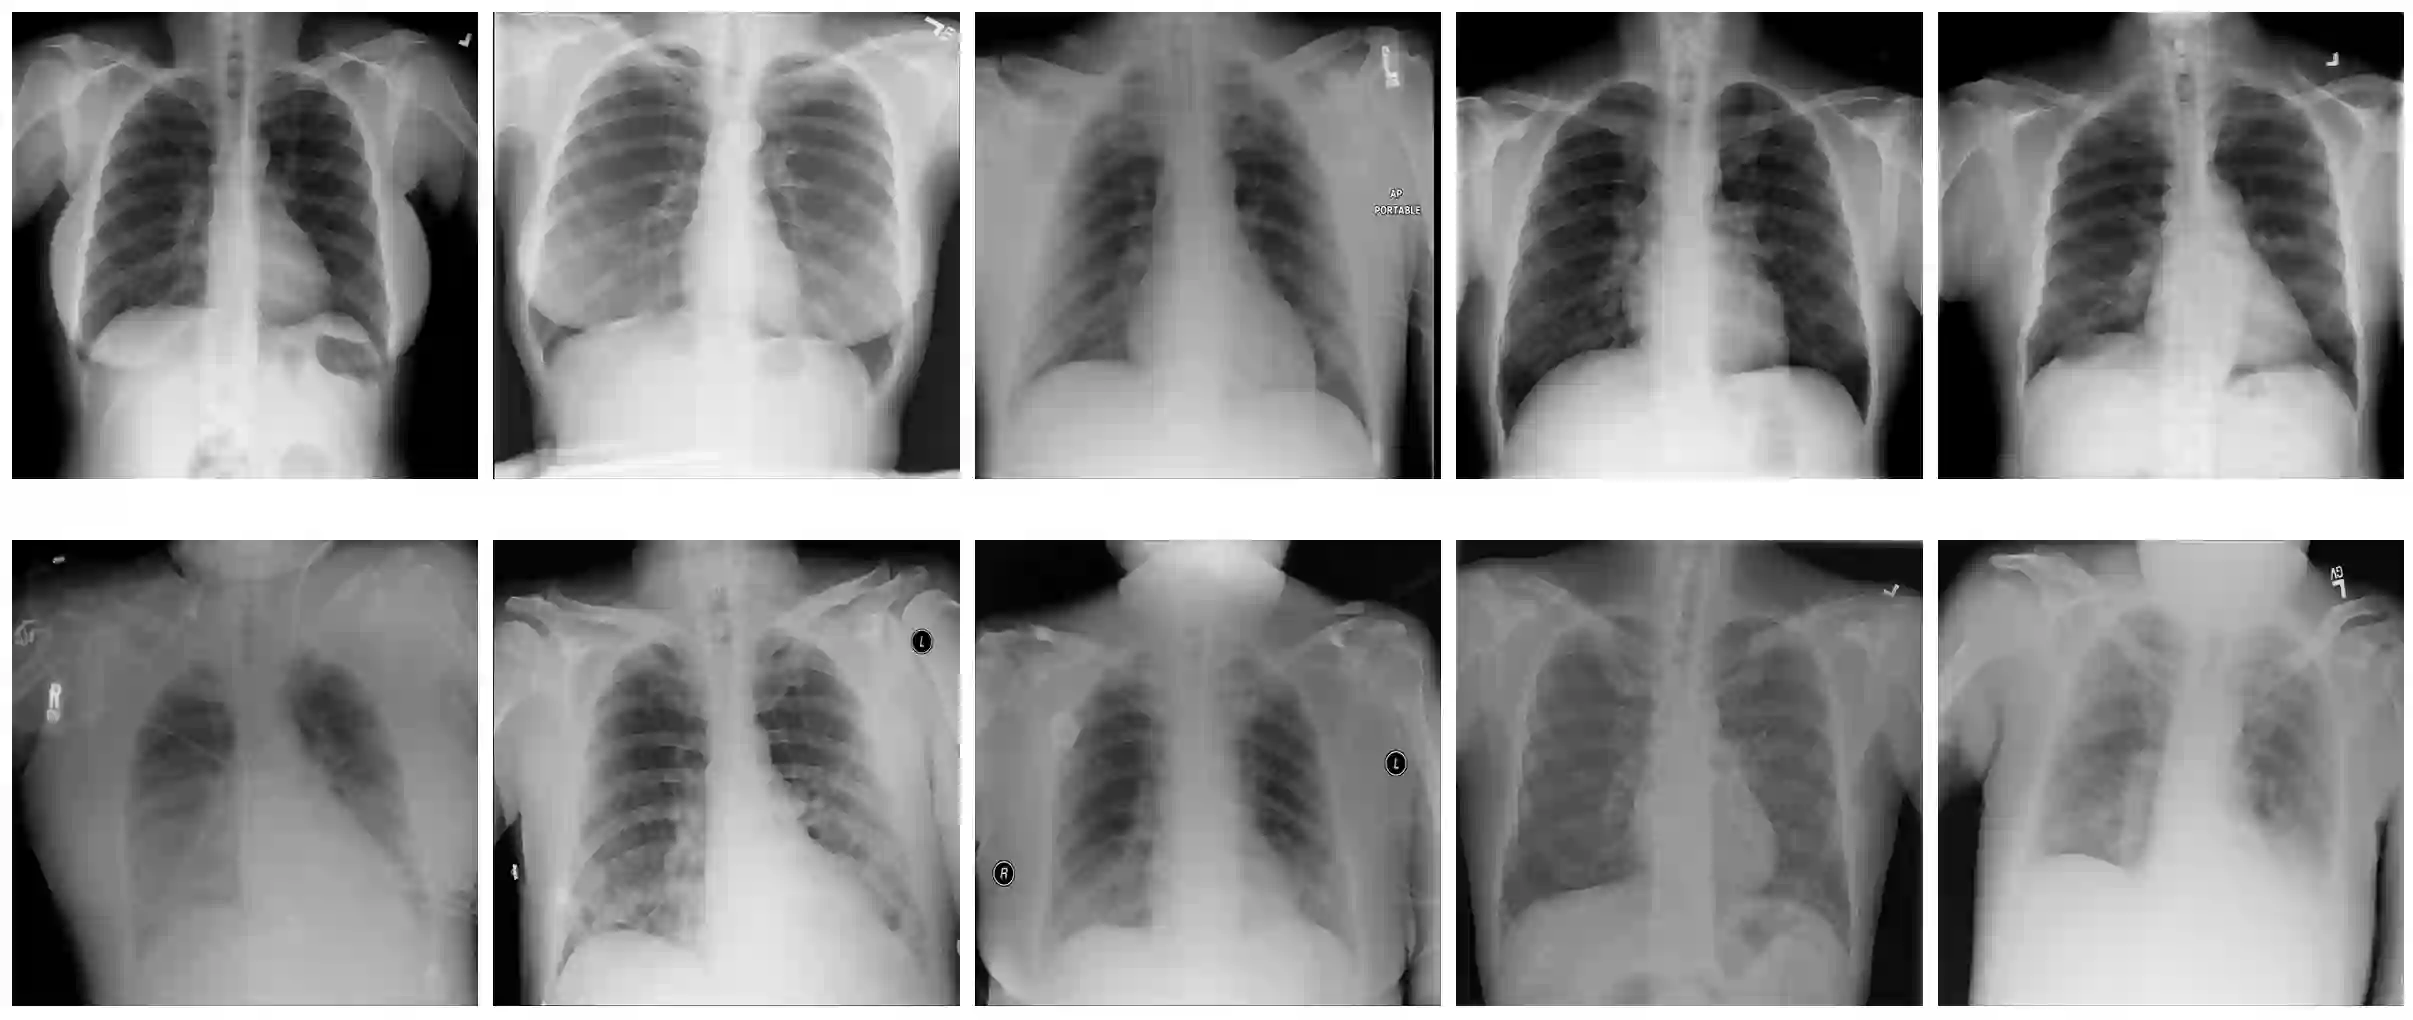

With the ongoing rise of machine learning, the need for methods for explaining decisions made by artificial intelligence systems is becoming a more and more important topic. Especially for image classification tasks, many state-of-the-art tools to explain such classifiers rely on visual highlighting of important areas of the input data. Contrary, counterfactual explanation systems try to enable a counterfactual reasoning by modifying the input image in a way such that the classifier would have made a different prediction. By doing so, the users of counterfactual explanation systems are equipped with a completely different kind of explanatory information. However, methods for generating realistic counterfactual explanations for image classifiers are still rare. Especially in medical contexts, where relevant information often consists of textural and structural information, high-quality counterfactual images have the potential to give meaningful insights into decision processes. In this work, we present GANterfactual, an approach to generate such counterfactual image explanations based on adversarial image-to-image translation techniques. Additionally, we conduct a user study to evaluate our approach in an exemplary medical use case. Our results show that, in the chosen medical use-case, counterfactual explanations lead to significantly better results regarding mental models, explanation satisfaction, trust, emotions, and self-efficacy than two state-of-the-art systems that work with saliency maps, namely LIME and LRP.

翻译:随着机器学习的不断兴起,对人工智能系统所作决定的解释方法的需要正在成为一个越来越重要的主题。特别是对于图像分类任务而言,许多最先进的解释这类分类工具依赖输入数据的重要领域的视觉突出显示。相反,反事实解释系统试图通过修改输入图像来促成反事实推理,使分类者能够作出不同的预测。通过这样做,反事实解释系统的用户配备了完全不同的解释性信息。然而,为图像分类者提供现实的反事实解释的方法仍然很少。特别是在医学方面,相关信息往往由文字和结构信息组成,高质量的反事实图像有可能为决策过程提供有意义的洞察力。在这项工作中,我们介绍了GANterfactal, 一种根据对抗图像到图像翻译技术产生这种反事实图像解释的方法。此外,我们进行了用户研究,以在典型的医疗使用案例中评价我们的方法。我们的结果显示,在所选择的医学案例中,反事实解释性解释方法往往包括文字和结构信息,高质量的反事实图像图像图像图像能够给决策过程带来更深刻的满意度,也就是两张的自我解释,而令人信得更满意。